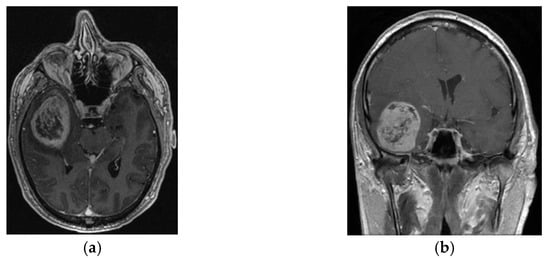

- Valerio, J.E.; Wolf, A.; Wu, X.; Santiago Rea, N.; Fernandez Gomez, M.; Borro, M.; Alvarez-Pinzon, A.M. Assessment of Gamma Knife Stereotactic Radiosurgery as an Adjuvant Therapy in First-Line Management of Newly Diagnosed Glioblastoma: Insights from Ten Years at a Neuroscience Center. Int. J. Transl. Med. 2024, 4, 298–308. [Google Scholar] [CrossRef]